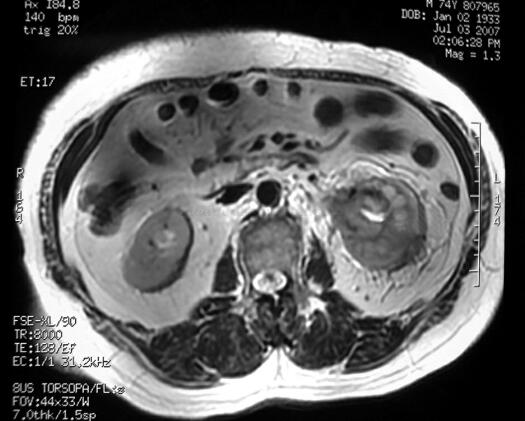

MR(图2):左肾盂、肾盏及肾周间隙病变,范围约4.5cm×3.5cm,形态不规则,边界不清,病变T1为等信号,T2低-等信号。动脉期有强化,实质期及延迟期增强更明显,肾周脂肪间隙见条索状强化。

图2 MR